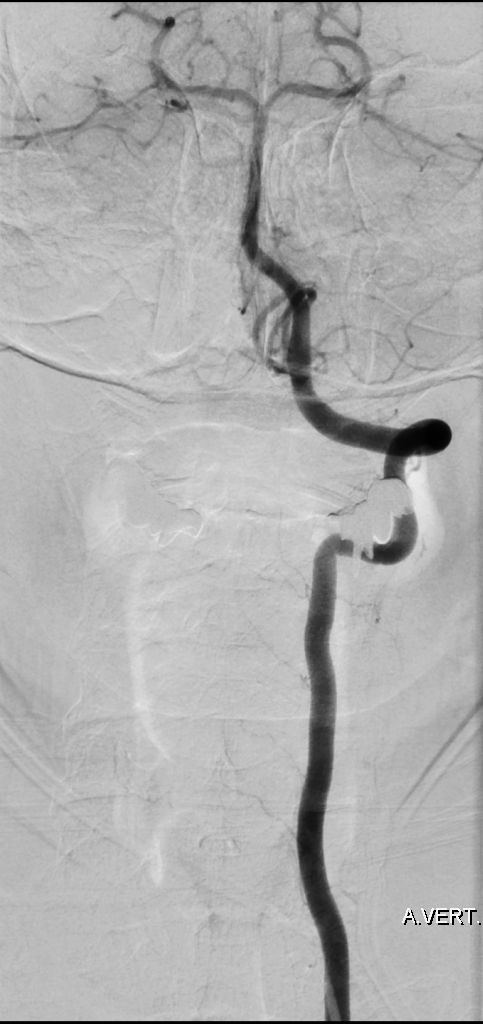

Bildgebung

Der Goldstandard zur optimalen Darstellung der Arteria vertebralis ist die digitale Subtraktionsangiographie, kann jedoch je nach klinischer Fragestellung auch in der CT-Angiographie oder MRT Bildgebung dargestellt wird.

Aneurysmen

Im Bereich der Arteria vertebralis können typischerweise Dissektionsaneurysmen auftreten und eine Subarachnoidalblutung verursachen[^3]. Die Behandlung dieser Dissektionsaneurysmen kann je nach Fall beispielsweise endovaskuläre mithilfe von Implantation eines Flow-Diverters behandelt werden[^4] [^5].